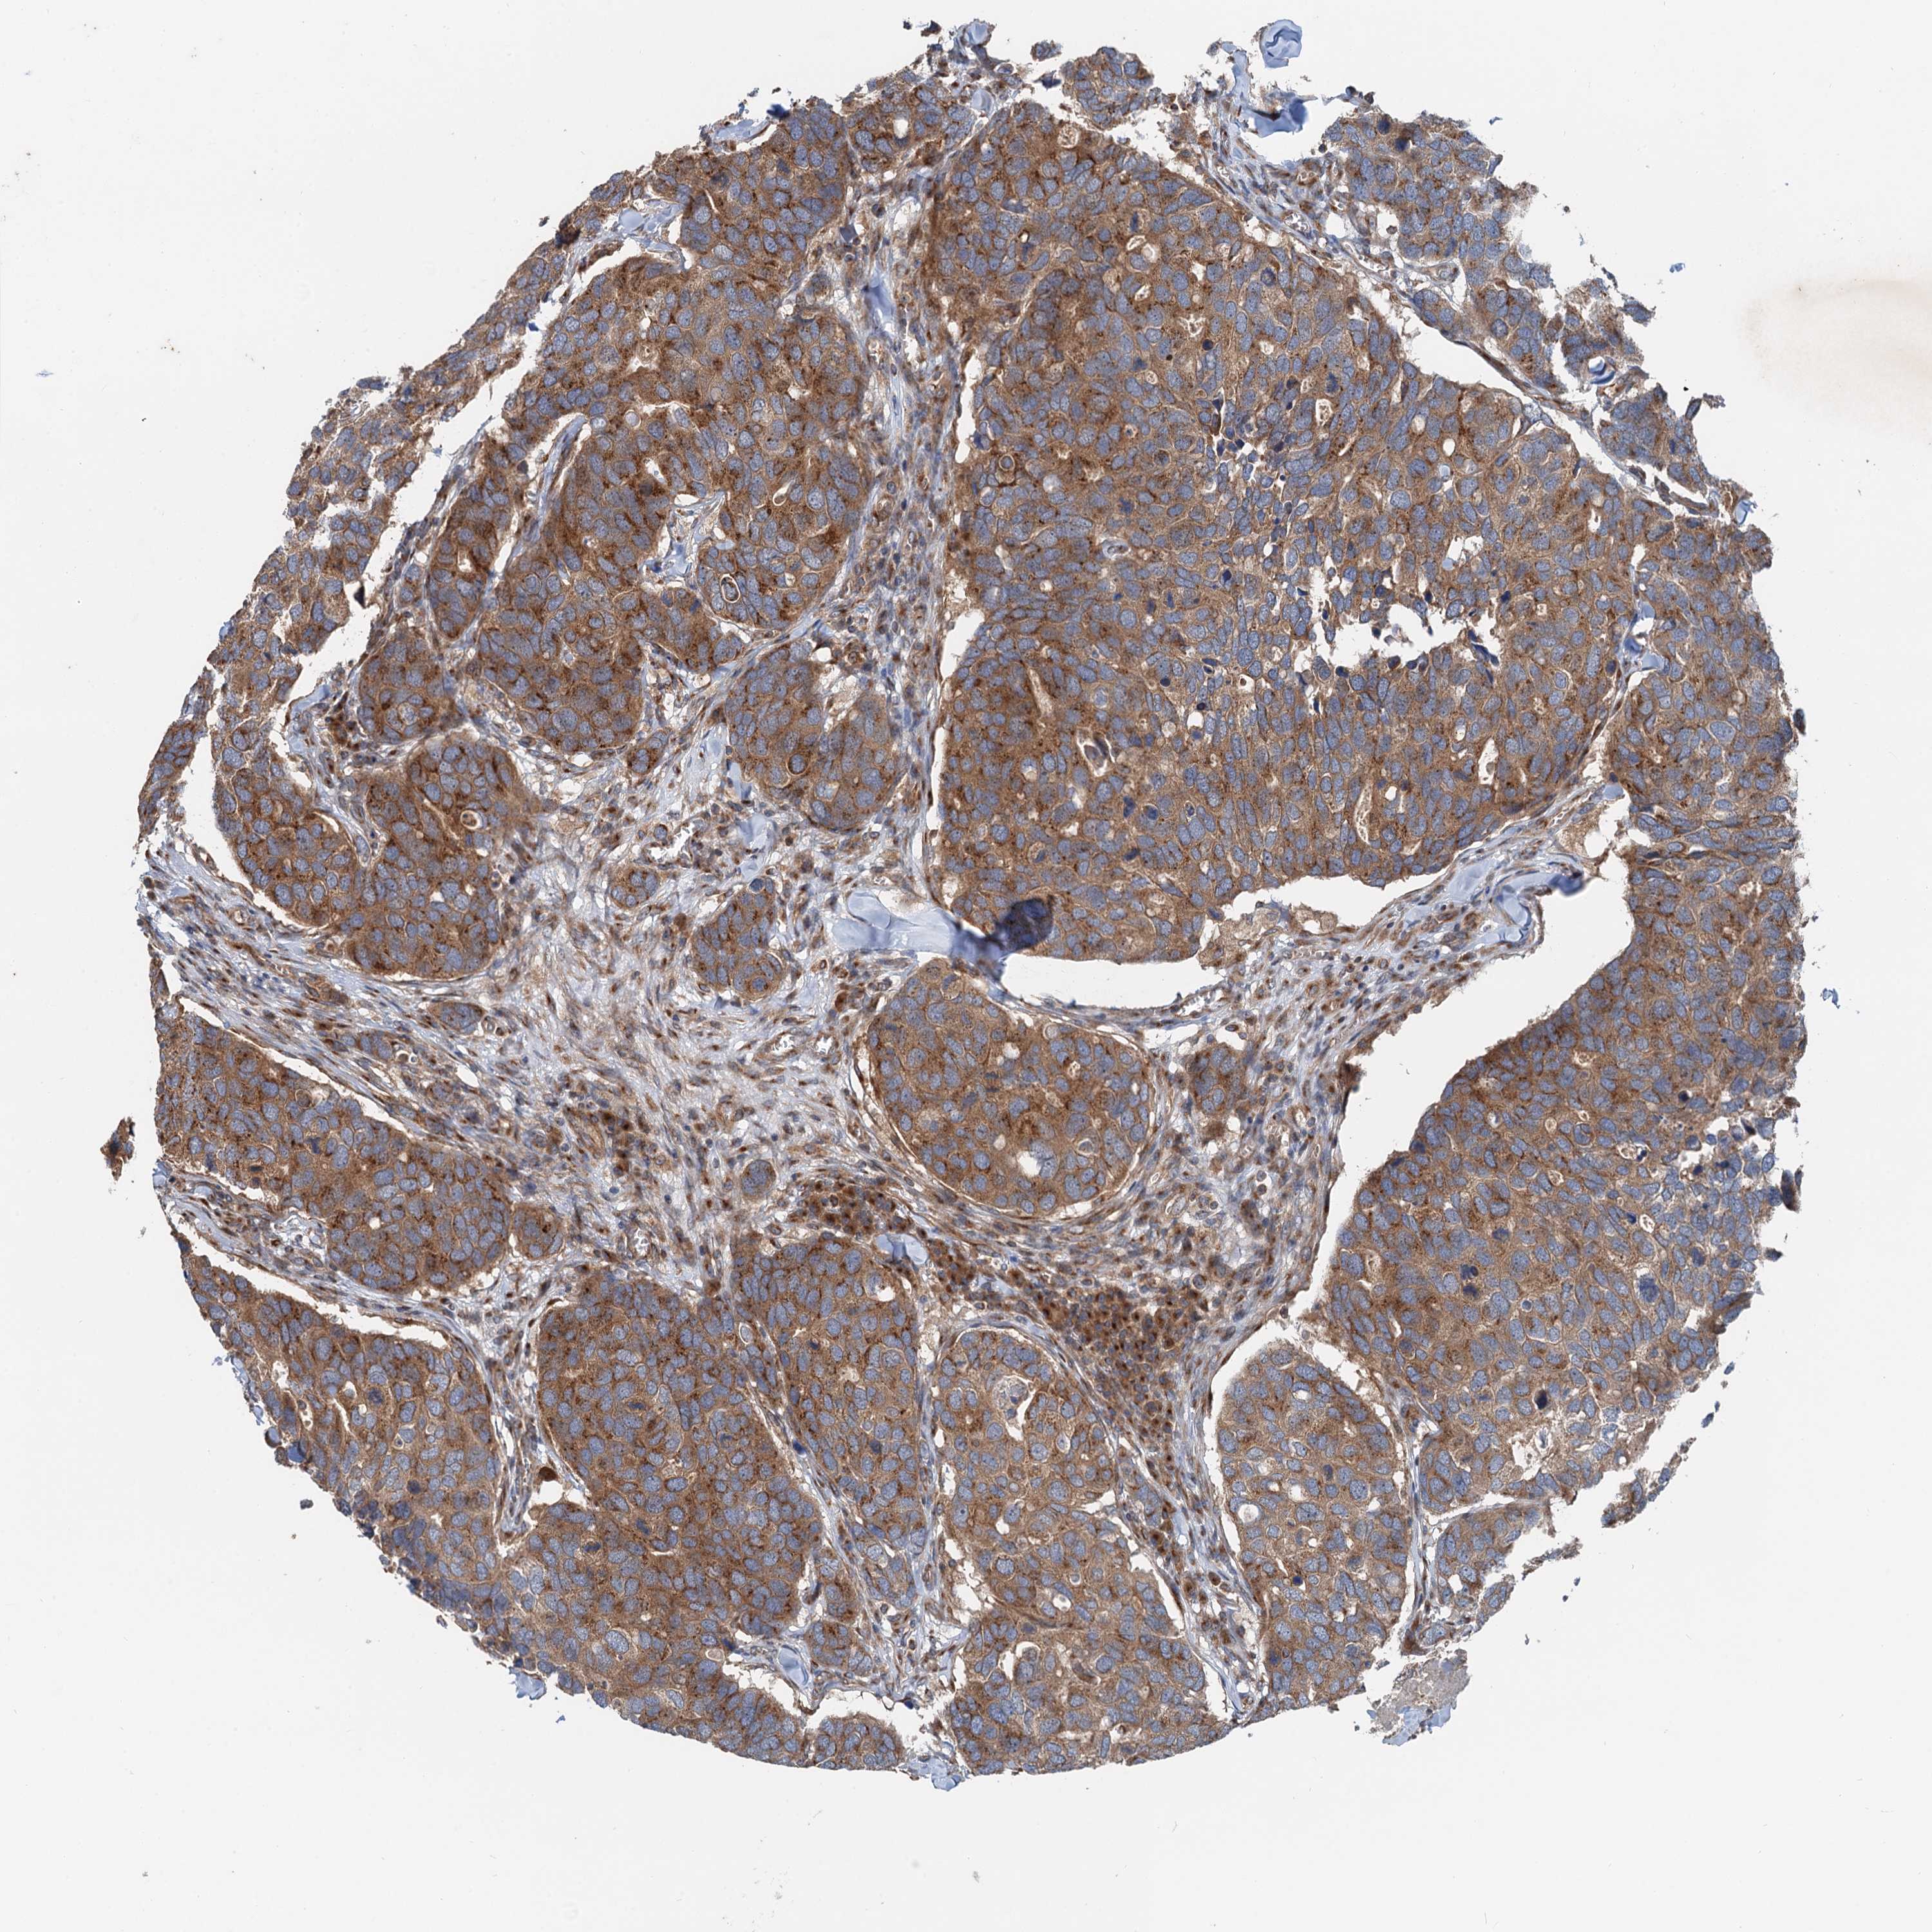

CANCER BREAST CANCER Show tissue menu

BRCA TCGA BRCA VALIDATION PROTEIN EXPRESSION